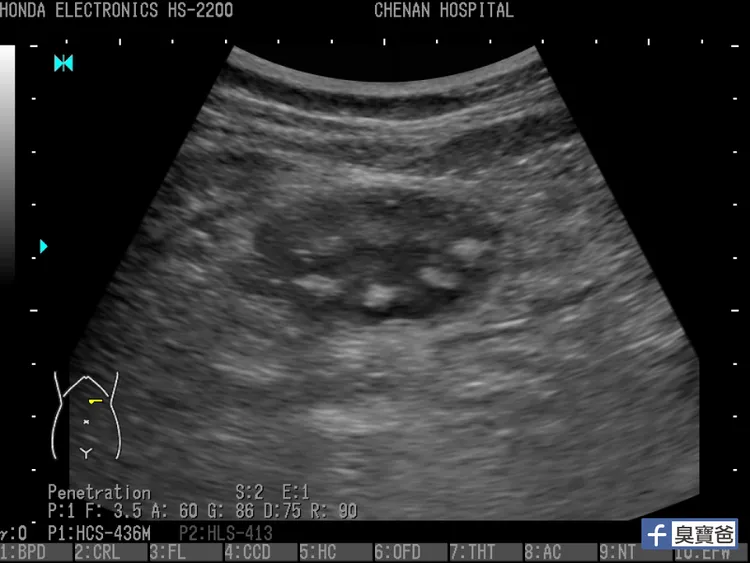

但是,「只有一個例外,珍珠奶茶的珍珠」陳敬倫說,「不容易消化,如果孩子吃了太多珍珠,就會在胃裡看到一顆一顆的珍珠,像是蓮蓬的影像」。近來可能因天氣熱,喝太多珍奶肚子痛的小孩也變多了,陳敬倫提醒,「對兒童來說,珍珠本來就不易消化,珍珠奶茶也含咖啡因,不適合孩子過度飲用喔!」